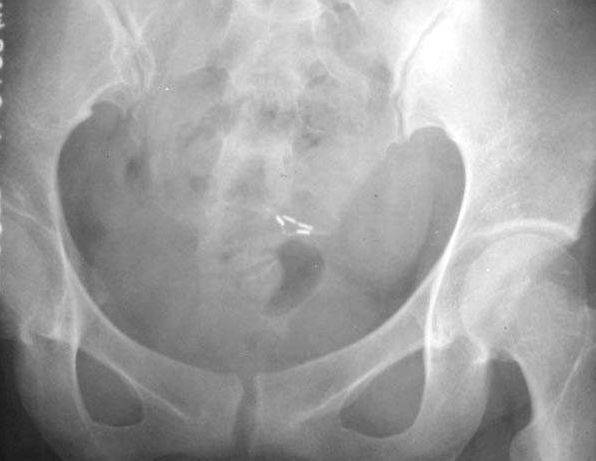

照片名称:输尿管结石

照片名称:输尿管结石3

照片名称:输尿管结石5